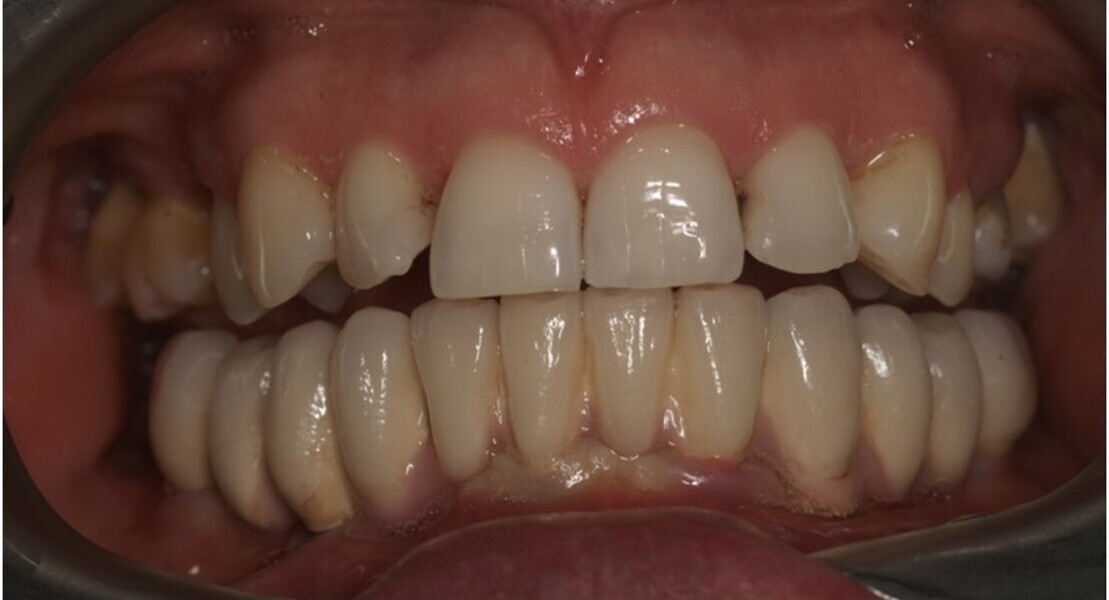

Natychmiastowa implantacja i zaopatrzenie protetyczne pacjentów z zaawansowaną chorobą przyzębia